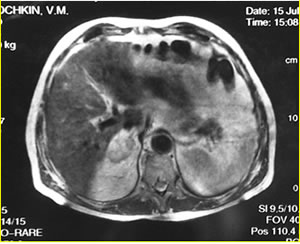

МРТ

забрюшинного пространства

Опухолевый узел левой почки

Mts в правый надпочечник